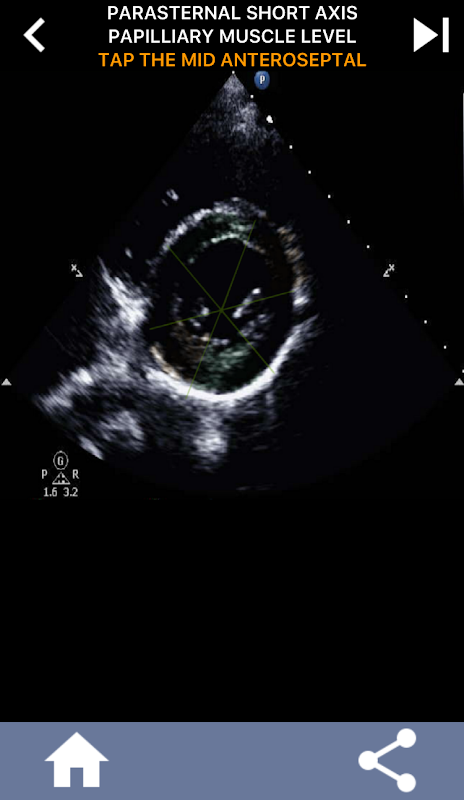

Enfoque visual basado en cuestionarios para aprender los segmentos cardíacos de la AHA: ecocardiografía

Esta comprensión se vuelve particularmente crucial cuando el cardiólogo busca determinar la ubicación precisa de un problema o cuando el médico de guardia identifica un problema dentro de una región específica, lo que hace que el ecografista muestre con precisión el segmento correspondiente, como la pared inferior media. Por lo tanto, poseer una comprensión integral de los segmentos cardíacos de la AHA es un conjunto de habilidades esencial.

Esta aplicación pondrá a prueba su conocimiento utilizando imágenes de eco reales, que a menudo encuentro que es el mejor método de enseñanza.